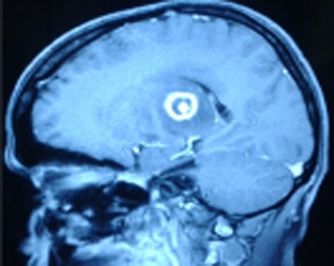

HIV. The number of hospital acquired infections is also on the rise. Opportunistic fungal infections like

candidiasis, aspergillosis, mucormycosis are no longer rare infections due to the growing population of

immunocompromized patients.